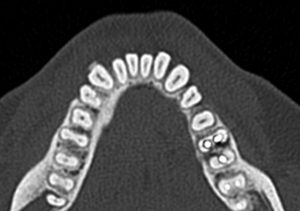

「断層撮影」は見たい部分を

輪切りにして画像化できるため、

見たい部分の厚みや深さ、

奥行きなどの情報を得ることも可能です。

埋伏歯をCTで撮影することには

以下のような利点があります✨

1. 正確な位置がわかる

CTスキャンは3Dの画像のため、

埋まっている歯の正確な位置を把握できます。

これにより、歯がどの方向に埋まっているのか、

他の歯や骨との位置関係を

はっきりと知ることができます。